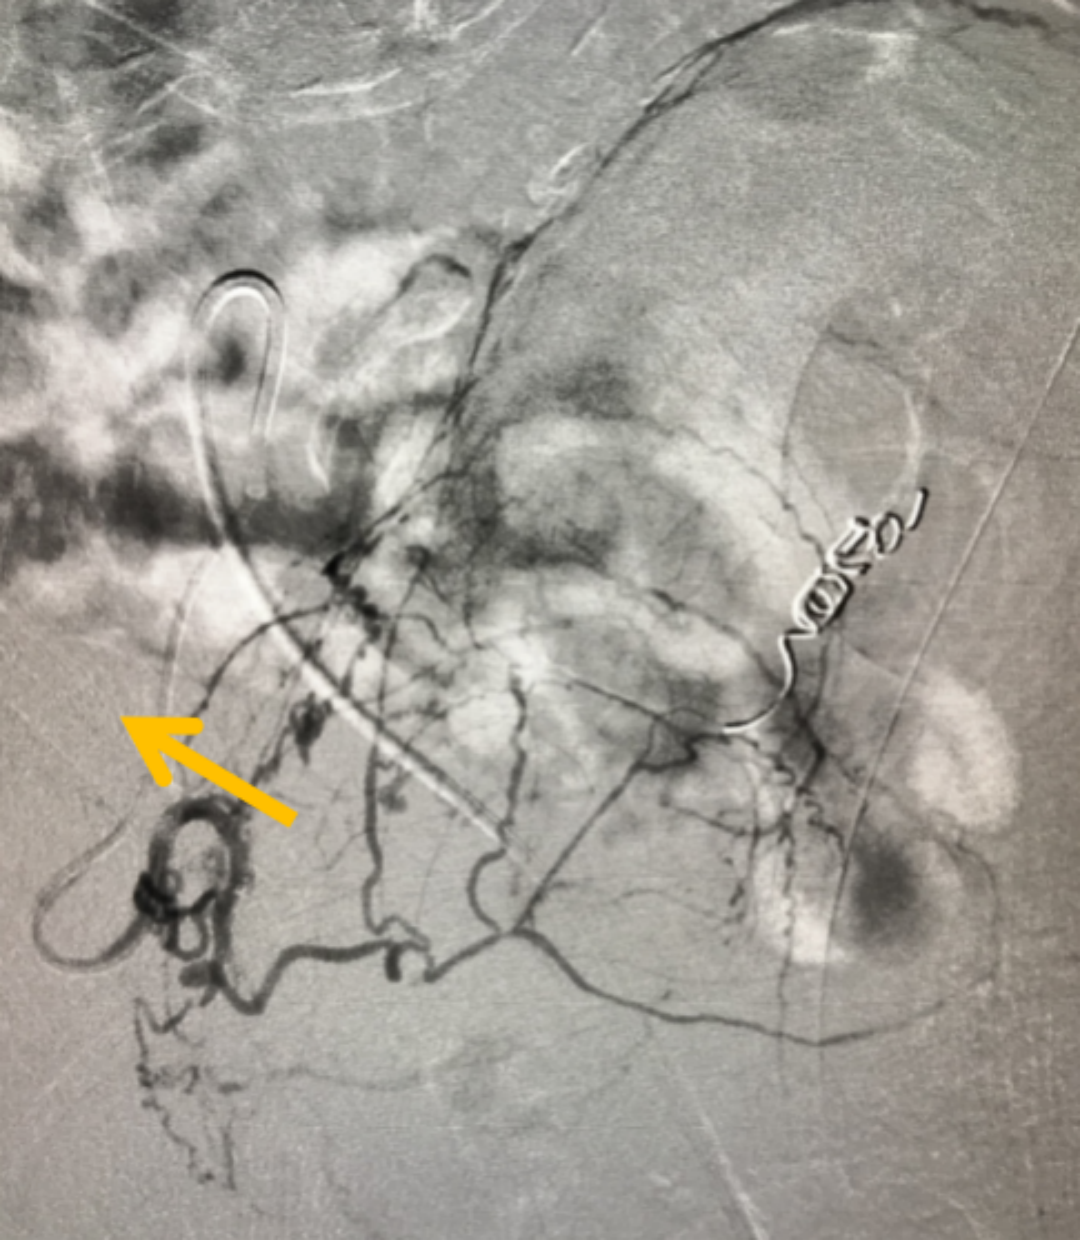

在全面评估后,团队为他制定了PAE的精准治疗方案。手术仅通过大腿根部一个针眼大小的穿刺点,将比头发丝还细的微导管,在影像引导下精准送入供养前列腺的动脉,并注入安全的栓塞微粒。这个过程,就像精准地“断粮”

图:微导管(箭头所指)